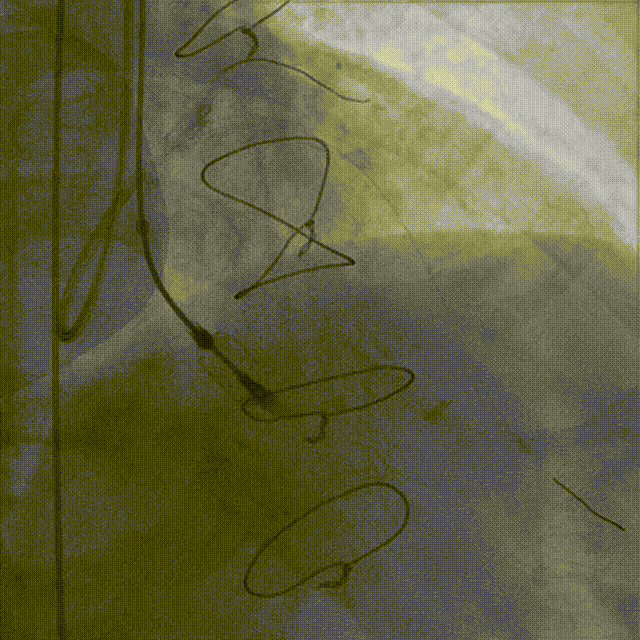

StagePCI时发现右冠病变更为复杂

经旋磨技术处理,右冠CTO开通过程和最后结果